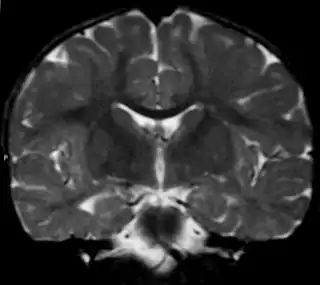

Imagen de una leucodistrofia en una niña de 18 meses. Posible Enfermedad de Alexander | ||

El diagnóstico había sido durante mucho tiempo difícil, debido a que la mayoría de los signos podían darse también en otras leucodistrofias, de modo que la prueba diagnóstica de confirmación consistía en una biopsia cerebral que revelara las fibras de Rosenthal. En ocasiones esto se efectuaba post mórtem en la necropsia. Sin embargo, esta prueba resulta bastante invasiva y se vio la necesidad de buscar otras posibilidades aprovechando las nuevas técnicas de imagen por MRI. En marzo de 2001 la eminente neuróloga Marjo van der Knaap y su equipo pudieron establecer una serie de criterios que probaban en un 90% de los casos la existencia de la enfermedad.[11] Se considera que la presencia de al menos 4 de los siguientes criterios dan un resultado diagnóstico positivo:

- Presencia de anormalidades extensas en la materia blanca con una preponderancia frontal o bien en cuanto a la extensión de estas anormalidades, en el grado de abultamiento, en el grado de cambio de señal o en el de pérdida de tejido (por atrofia o degeneración cística).

- Presencia de un borde periventricular de descenso de intensidad de señal en las imágenes potenciadas en T2 y elevación de la intensidad en imágenes potenciadas en T1.

- Anormalidades en los ganglios basales y tálamos, consistentes en una elevación en la intensidad de la señal y abultamiento o en atrofia y aumento o descenso de la intensidad de la señal en imágenes potenciadas en T2.

- Anormalidades en el tronco encefálico, en particular incluyendo el cerebro medio y la médula.

- Aumento de contraste que implica uno o más de las siguientes estructuras: borde ventricular, cerco de tejido periventricular, sustancia blanca de los lóbulos frontales, quiasma óptico, fórnix, ganglios basales, tálamo, núcleo dentado y estructuras troncoencefálicas.